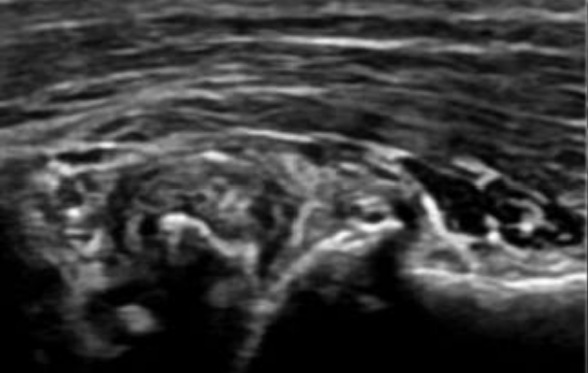

几种典型肌骨超声图片:

滑膜炎是因为关节内的滑膜受到外伤等刺激因素,产生炎症,造成分泌液失调,形成积液的一种病变,主要表现为关节处的疼痛、肿胀、局部温度升高以及关节活动受限等。滑膜炎主要可分为膝关节滑膜炎、髋关节滑膜炎、踝关节滑膜炎。